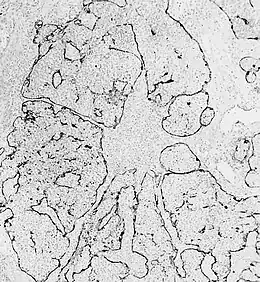

Esthésioneuroblastome.

L'esthésioneuroblastome (ou neuroblastome) olfactif est une tumeur rare se développant aux dépens du nerf olfactif dans la cavité nasale. Moins de 1 000 cas dans le monde ont été publiés durant les vingt dernières années[1]. Les causes de cette tumeur restent inconnues. La pathologie a été décrite pour la première fois dans la littérature par Berger et Luc en 1924[2].